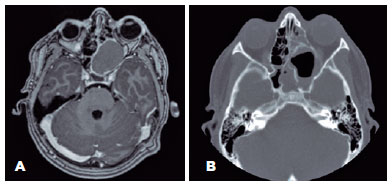

Subsequently, computed tomography (CT) and magnetic resonance imaging (MRI) scans of the patient’s head were performed, resulting in the discovery of a unique cystic mass of benign appearance with dimensions of 39.91 mm x 25.55 mm x 51 mm. The mass occupied the left sphenoid, left maxillary, and ipsilateral posterior ethmoidal sinuses, displacing and deforming the intraconal area of the left orbit. This suggested SSM (Figure 2A). The mass was also compressing the optic nerve and causing left globe proptosis, deforming the medial orbital wall but without bone erosion. The mass had not infiltrated the vascular, muscular, or nervous tissue. The optic nerve chiasma was unaffected.

01-fig02.jpg)

The mass was well defined, with smooth thin walls and peripheral enhancement. No diffusion restrictions were found, ruling out a dermoid or epidermoid tumor. The CT and MRI echo gradient sequences indicated the absence of calcium and there was no internal bleeding or vascular involvement.

A postoperative CT scan of the patient’s head revealed residual bone remodeling. The hollow cavity comprised two parts divided by high-density lobulated postsurgical debris and a hydro-air level in the external and anterior aspects. The distortion to the medial orbital wall had rectified slightly and the compression on the orbital cone was relieved. There were no intracranial or extracranial postoperative complications (Figure 2B).